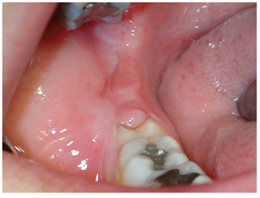

OROFACIAL SWELLING:- Abnormal enlargement of facial tissue caused by infection, inflammation or trauma. It can be intraoral or extraoral. It should be treated as soon as possible as it can be a cause of severe infection.

CELLULITIS:

Bacterial infection in oro-facial region leads to formation of abscess and swelling.